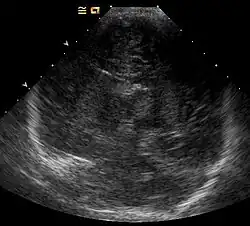

Bildgebende Verfahren können bereits im Alter von wenigen Monaten in der Sonographie und später in der Magnetresonanztomographie Veränderungen mit typischen Lokalisationen an Hirnstamm und Basalganglien, sowie Zeichen der Leukodystrophie ergeben und zur Diagnose beitragen.[8]